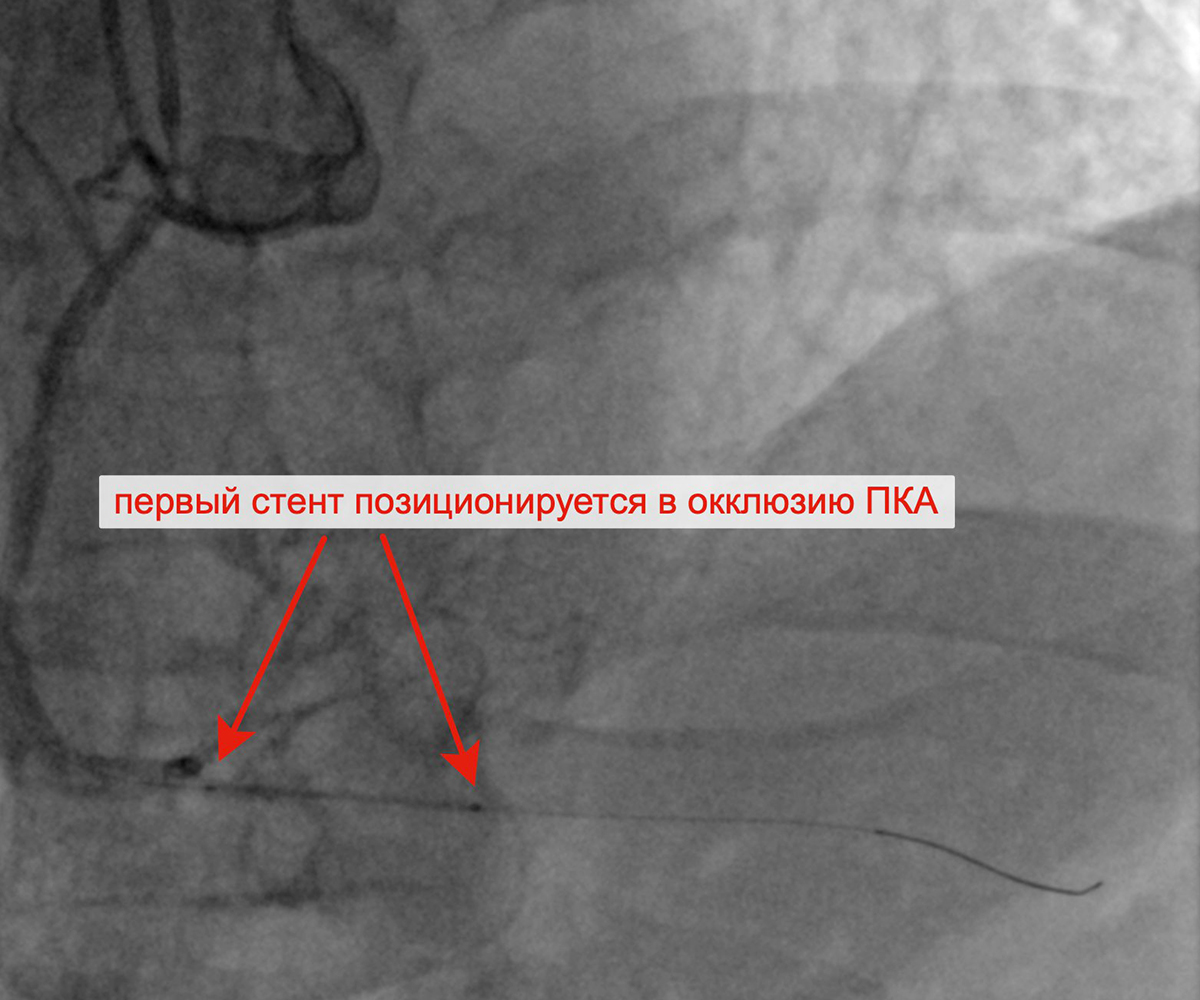

Чрескожное коронарное вмешательство (ЧКВ) на хронической окклюзии ПКА выполнялось билатеральным лучевым доступом: через левую лучевую артерию диагностическим катетером параллельно выполнялись съемки ЛКА, что позволило визуализировать через межсистемные коллатерали дистальное русло постокклюзированной ЗМЖА и контролировать процесс реканализации хронической окклюзии и проведение коронарного проводника в дистальное русло ЗМЖА. Успешно была выполнена реканализация ЗМЖА, баллонная ангиопластика и стентирование правой коронарной артерии (3 стента с лекарственным покрытием). При контрольной ангиографии: стенты и ПКА проходимы, позиционирование стентов адекватное, диссекции или остаточного стеноза в стентированных сегментах ПКА нет, кровоток TIMI 3 по ПКА и всем ветвям. Пациент был на следующий день выписан из клиники.

Позиционирование первого стента в ПКА после предилатации Позиционирование второго стента в ПКА

с билатеральным контрастированием